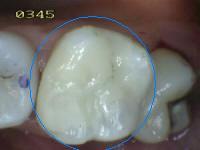

2. SOMBRA SUBYACENTE DE DENTINA (SIN PERDIDA DE INTEGRIDAD ESTRUCTURAL)

1. HALLAZGO: sombra que trasluce una restauración

1. CRITERIO DE DIAGNOSTICO: área oscurecida, sombra intrínseca, que puede aparecer gris, azúl o café

1. ICDAS 4

2. DIAGNOSTICO

1. lesión cariosa no cvitacional

2. TRATAMIENTO

1. Operatorio